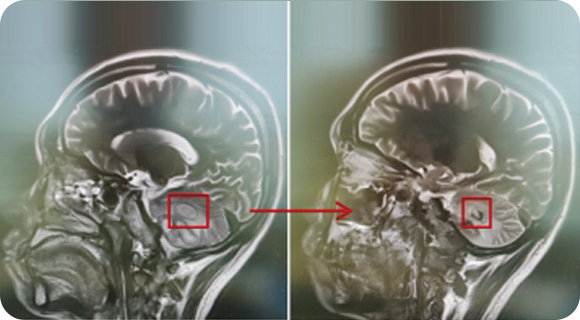

精通颅内动脉瘤介入栓塞和手术夹闭双技术,系统掌握脑动静脉畸形、颈内动脉海绵窦漏、硬脑膜动静脉漏等颅内血管疾病的诊疗和手术,精通颈动脉、椎动脉狭窄的血管内重建技术,以及颈动脉狭窄的内膜剥脱手术技术。在颅内肿瘤、椎管内肿瘤、颅脑损伤、高血压脑出血等疾病的诊治和手术,脑功能性疾病立体定向手术治疗等方面也积累了丰富的经验。

擅长脑血管病(出血与缺血)的神经介入与微创手术,能熟练开展脑外伤、重度颅脑损伤的救治工作。